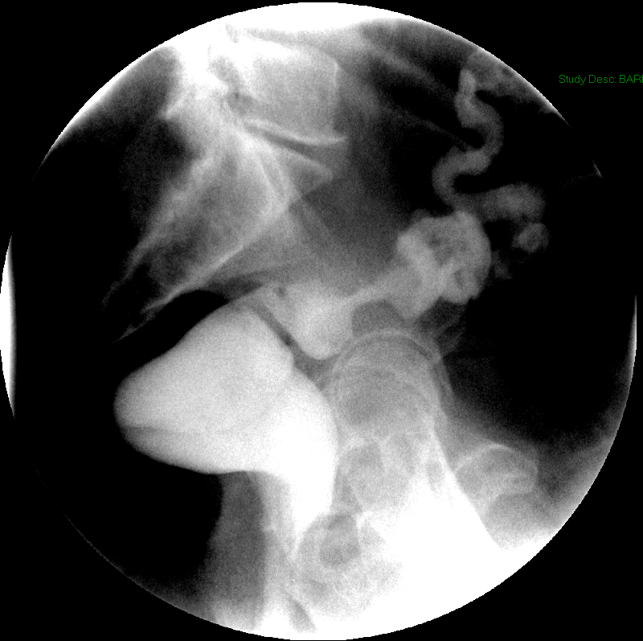

- Method—Cervical:

- Start with the patient in the upright lateral position.

- Ensure the fluoro machine is set to 4 images per second (rapid sequence).

- Explain to the patient that you are going to have them take a "comfortable mouthful" of barium and that they will need to hold it in their mouths until you count to 3.

- Make sure they understand that they are not to swallow until the count of 3.

- Once the patient has taken the "comfortable mouthful" of barium, center the fluoroscope on the cervical esophagus.

- Once the fluoroscope is properly positioned, begin counting. On the count of 2, begin taking rapid sequence images of the contrast material bolus as it moves through the cervical esophagus

(key image 1)

- Take the fluoroscope off rapid sequence.

- With the patient in the lateral position, obtain a spot film of the pharynx and cervical esophagus while they phonate the letter "e"

(key image 2).

- Repeat steps 4-7 with the patient in the AP position

(key image 3)

(key image 4).